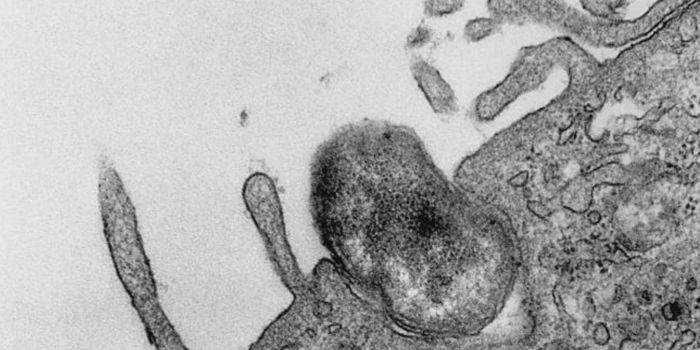

Another recent report published in Scientific Reports details novel technology allowing doctors to examine a type of breast cancer tissue that is usually challenging to evaluate.  The researchers focused on the mammary epithelial tissue, which is made up of cells involved in the development of breast cancer.

Mammary epithelial cells make up a thin layer of tissue lining the ducts which produce milk during lactation.  If the mammary epithelial cells grow uncontrolled, ductal carcinoma in situ (DCIS) arises.  DCIS is considered a pre-cancerous condition, but if these cells continue to progress and invade tissues beyond the epithelium, invasive intraductal breast cancer, the most common type of breast cancer, develops.  The researchers sought to evaluate the breast epithelial cells for factors associated with recurrence to provide a blueprint for doctors to better predict patients at high risk of recurrence.

Epithelial cells are inherently challenging to study as they grow slowly in culture and can be difficult to separate from other, faster-growing cells found in proximity.  This challenge prompted using a novel technique called epithelial-specific conditionally reprogrammed cells (CRC).  This method allowed the research team to explore the gene expression of the epithelial cells by transcriptional profiling, which quantifies various genes at the RNA level.